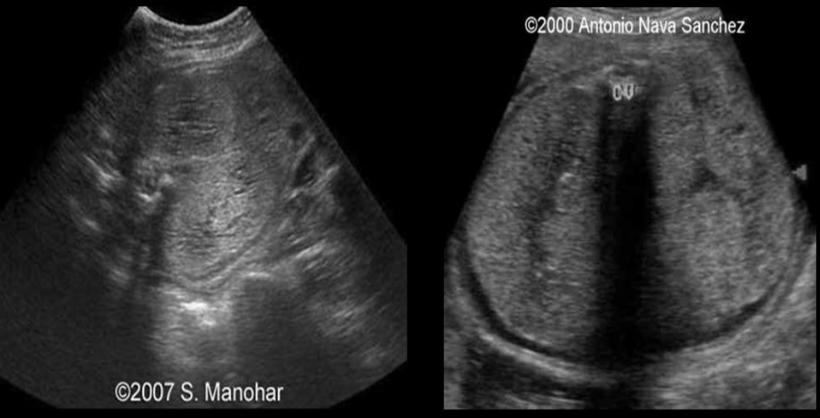

the color doppler portion shows

a) no pericallosal artery

b) thrombus of vein of galen

c) normal fetal anatomy

d) no circle of willis